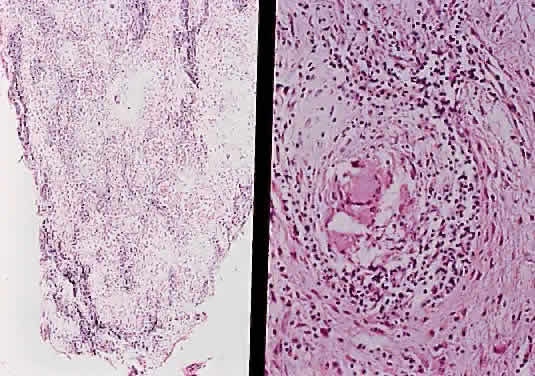

Grossly, optic gliomas that are confined to the orbit appear as fusiform, solid, and somewhat firm expansions of the optic nerve (Fig. 36). They usually blend imperceptibly with the grossly uninvolved nerve at either end. The enveloping dura may be stretched but is not breached. Microscopically, the tumor is composed of bipolar hair-like (pilocytic) astrocytes that infiltrate between preexisting axons and expand rather than compress the nerve fascicles. The neoplastic cells are only mildly atypical, and mitotic figures are typically absent. Not uncommonly, the tumor “spills over” into the subarachnoid space, forming a collar (Fig. 37).

Fig. 37. Pilocytic glioma of optic nerve (hematoxylin and eosin staining). Low power on left shows nerve surrounded by thickened meninges. High power on right shows spindle-shaped cells.